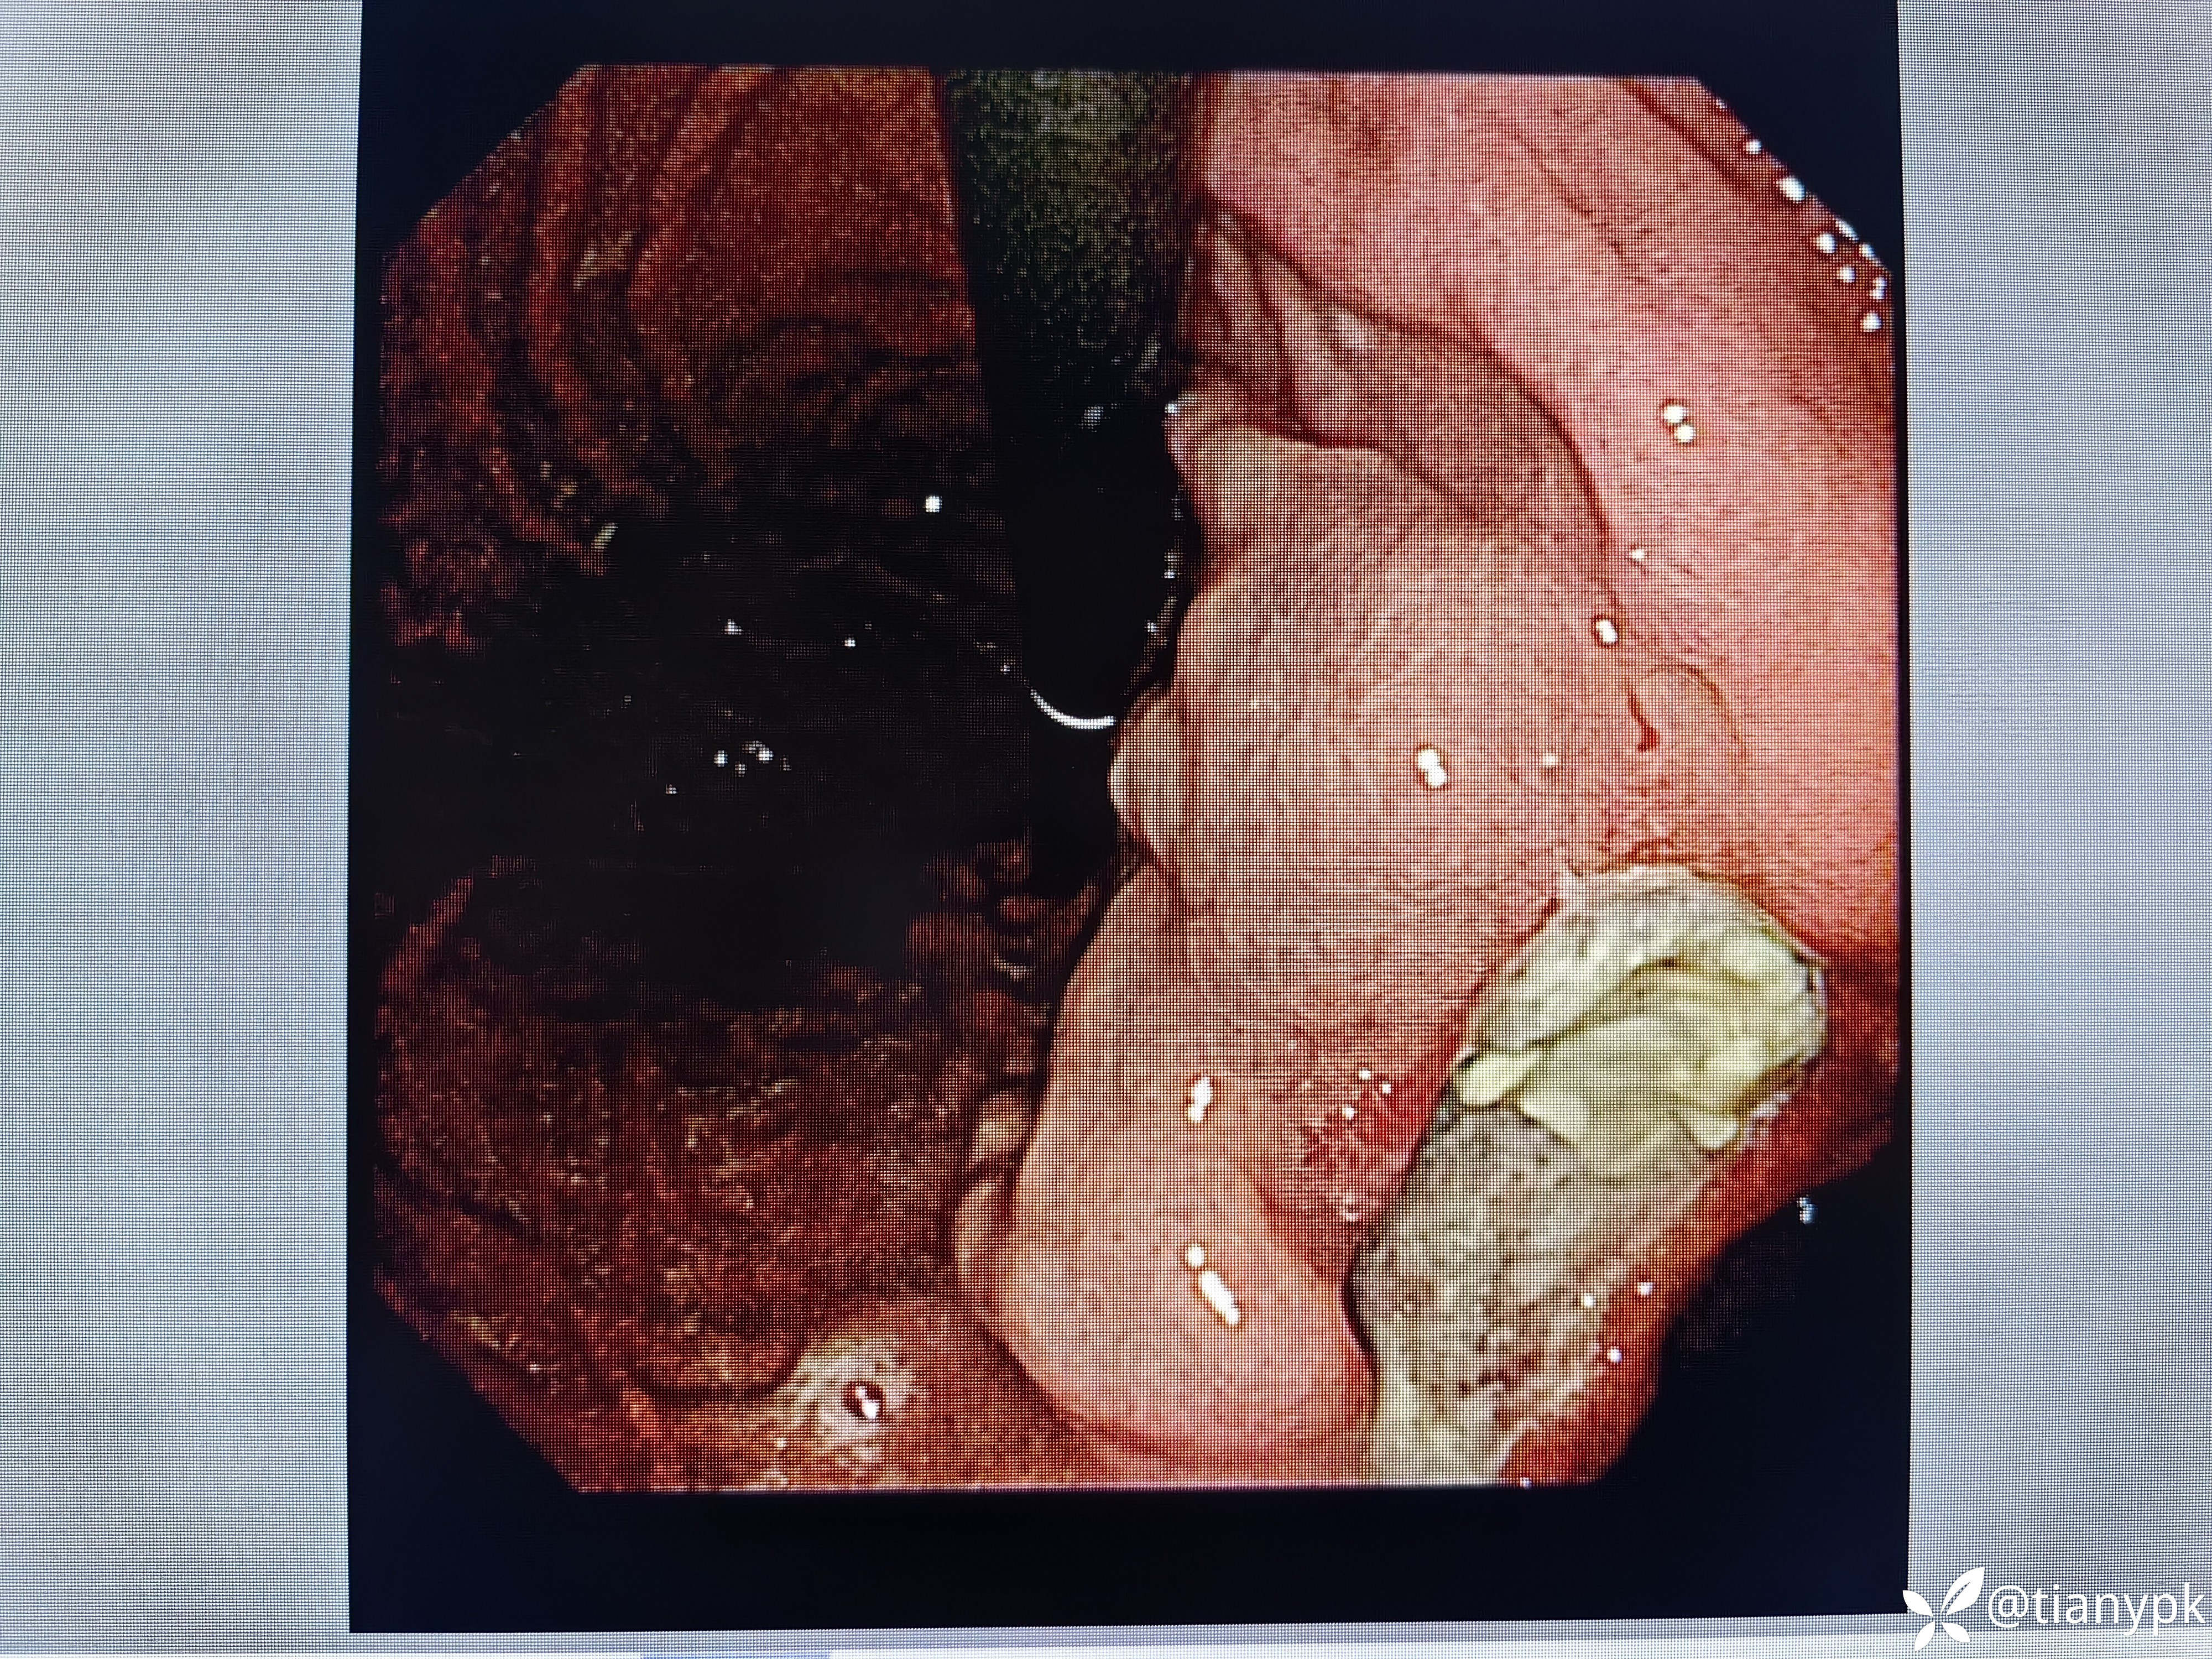

男性,54岁。

主诉:中上腹隐痛一周余伴大便发黑。

既往有乙肝,长期抗病毒治疗,否认近期明显消瘦。

胃镜检查如下:

胃角见巨大溃疡,良性?恶性?